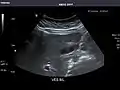

Left kidney